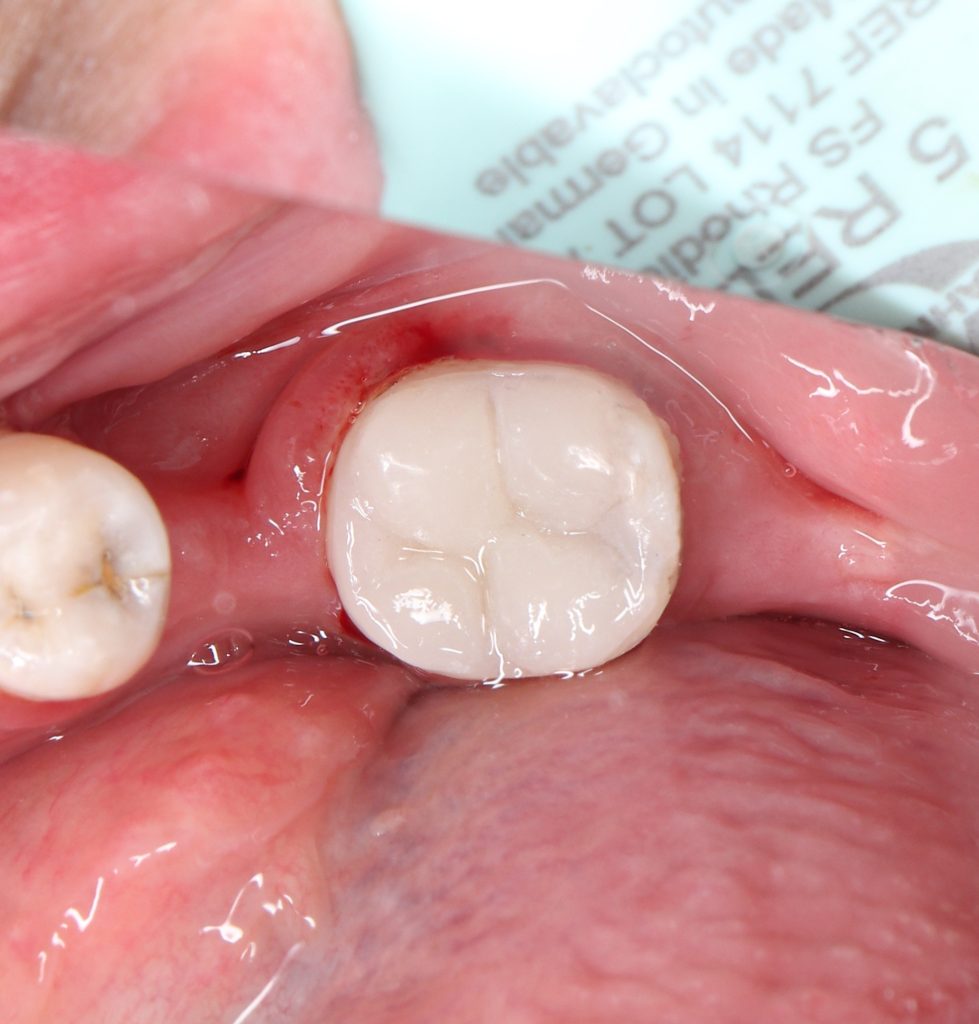

🔹Direct composite restoration